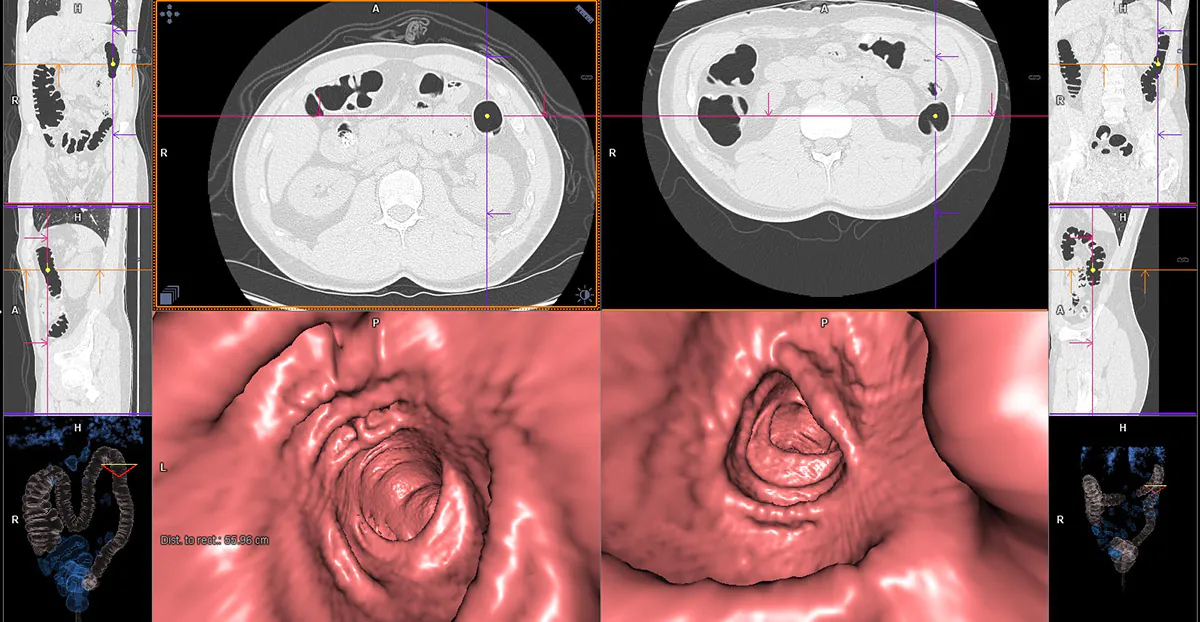

Colorectal cancer screening can be using radiological imaging techniques such as barium enema and visual colonoscopy. However, currently colonoscopy is the most widely used screening technique since, in addition to giving the most reliable results, it can treat patients with abnormalities in the large intestine.